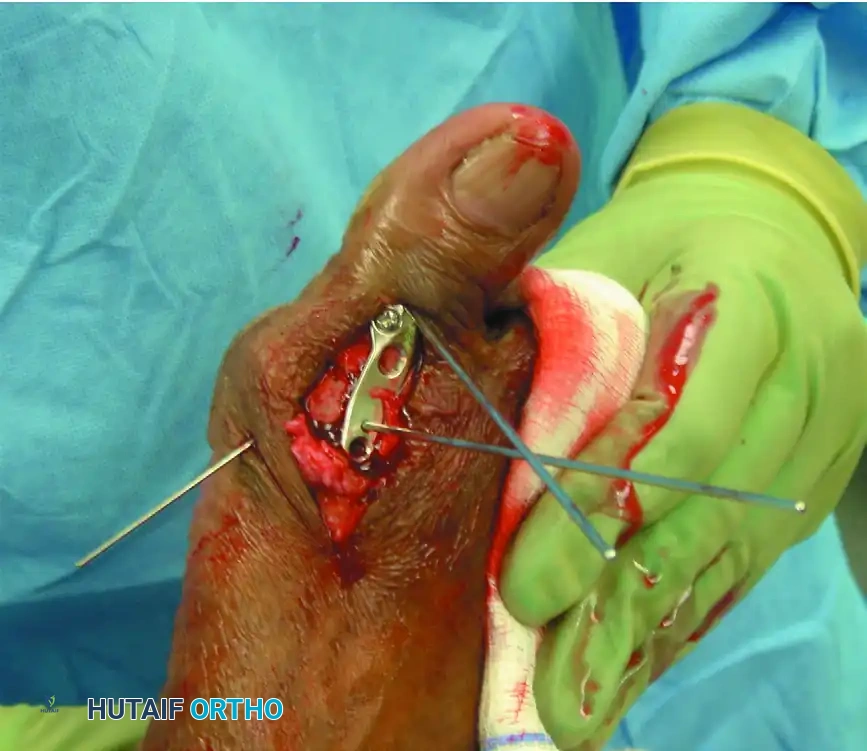

5. Definitive Internal Fixation

The method of internal fixation depends on surgeon preference, but the biomechanical gold standard is an obliquely placed headless compression screw combined with a precontoured dorsal neutralization plate.

Place the interfragmentary compression screw from distal-medial to proximal-lateral, ensuring it crosses the arthrodesis site and engages the thick lateral cortex of the metatarsal diaphysis. Predrill the near cortex before placement. Completely countersink the head of the screw into the proximal phalanx to prevent soft-tissue irritation.

Once interfragmentary compression is achieved, secure the precontoured, low-profile fusion plate to the dorsal aspect of the MTP joint using 2.7-mm to 4.0-mm multi-use compression or locking screws. In patients with osteopenia or poor bone quality, utilize larger screw sizes or locking technology to gain additional purchase and prevent hardware pullout.

Proceed with internal fixation of the first MTP joint using the lag screw and dorsal plate construct described in Technique 84-2. For the lesser toes, fixed hammer toe deformities are corrected by resecting 30% to 40% of the distal aspect of the proximal phalanx (the phalangeal bases are intentionally preserved to maintain soft tissue tension).